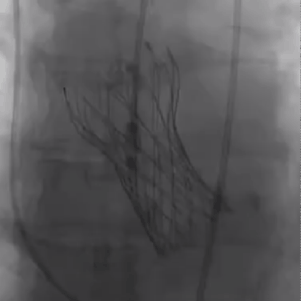

从三叶瓣重度钙化到二叶瓣畸形的根部解剖,从单纯主动脉瓣反流到入路极端迂曲挑战的案例。TaurusOne凭借其优异的柔顺性,支撑力强及内外层双侧裙边的特点,都能从容应对复杂的临床患者解剖结构。从患者的临床选择到术后的长久获益,从手术入路的种类到术中操作的注意事项,从围术期卒中的循证医学到术后的抗凝抗栓用药规范,在线专家共同交流彼此中心的围术期TAVR经验和分享现阶段经导管主动脉瓣置换的诊疗策略。针对当前TAVR领域多个热点学术问题进行了热烈的讨论,现场可谓精彩纷呈、高潮迭起。专家们纷纷借此契机相互交流探讨,分享各自的单中心经验,力求进一步提升TAVR手术的安全性和有效性,为主动脉瓣相关疾病的患者带来长远综合获益。